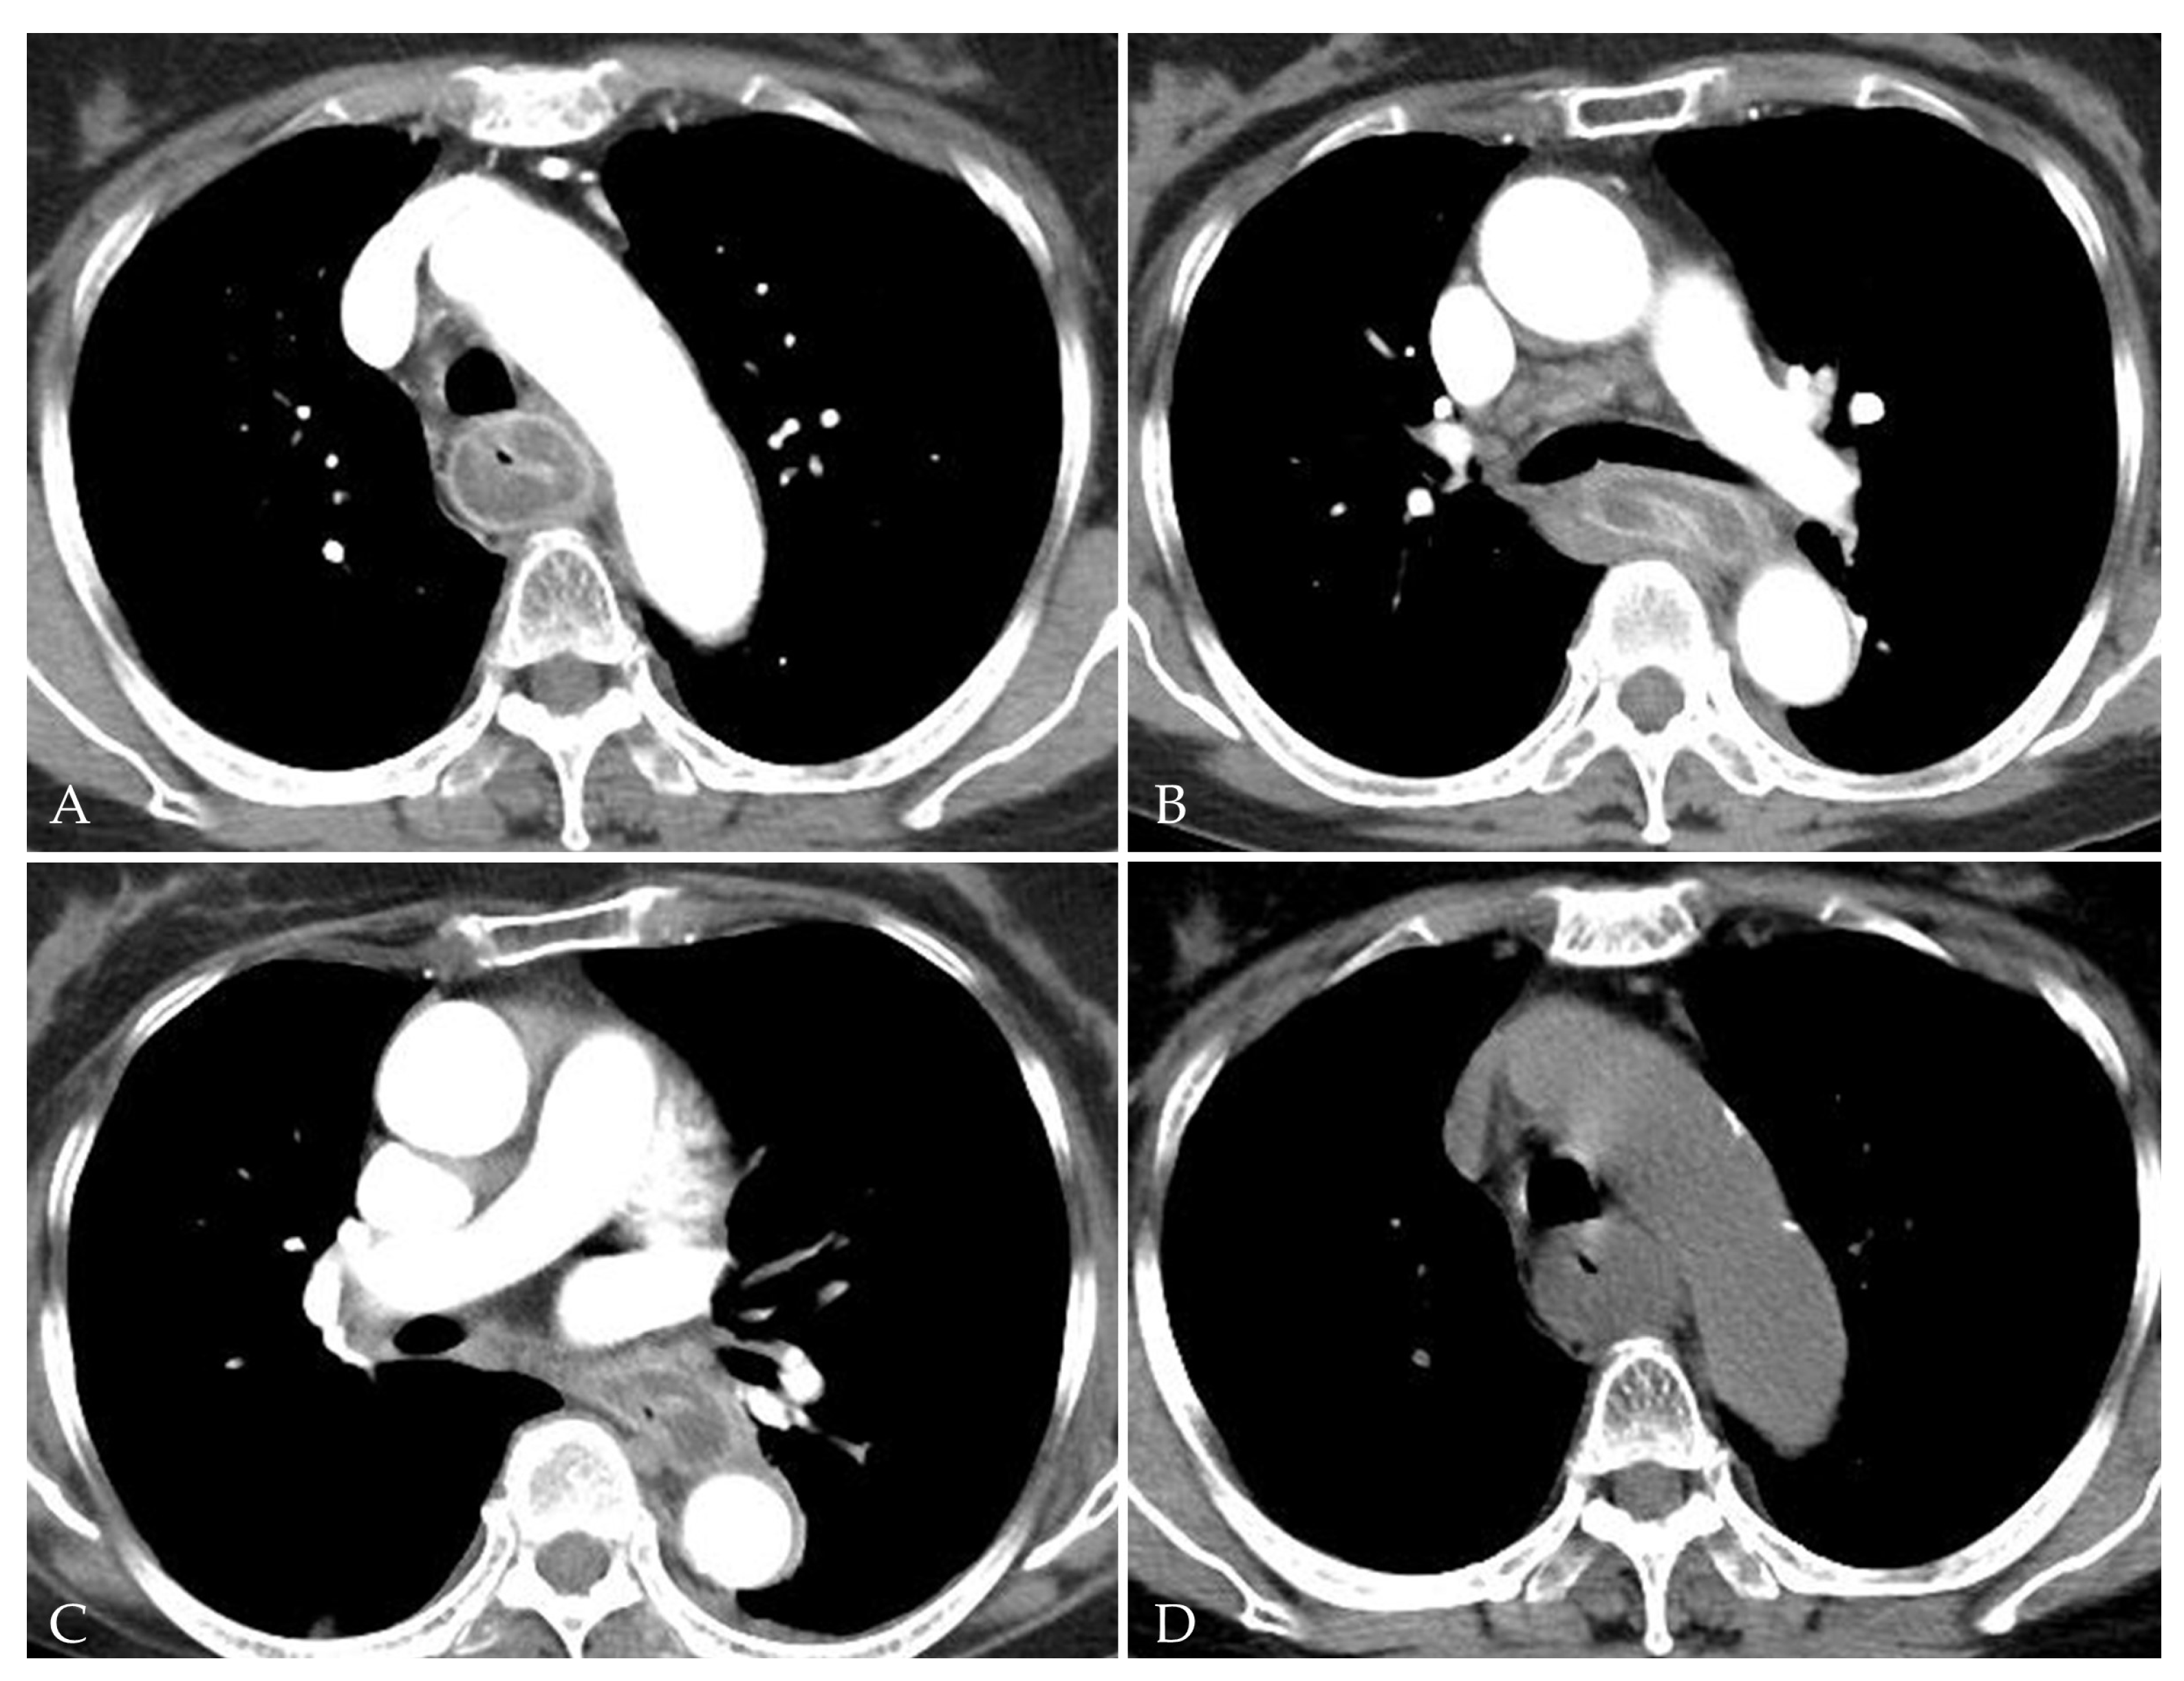

2. Detailed Case Description